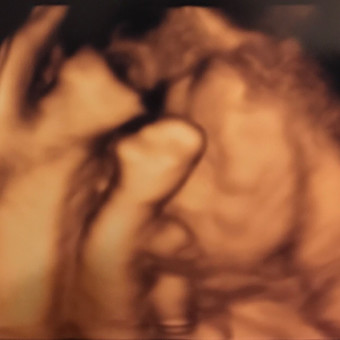

We're excited to welcome our new son and daughter this Spring 😄